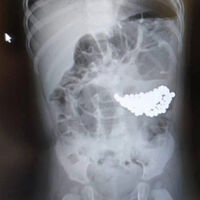

В Ямало-Ненецком автономном округе двухлетний мальчик проглотил 18 магнитов и не выжил. Об этом сообщает Telegram-канал «Реальный Ноябрьск».

По информации канала, инцидент произошел в поселке Пурпе. Родители двухлетнего ребенка обратились за медицинской помощью для сына сразу, как заметили пропажу магнитов-бусинок. При этом мальчик якобы вел себя, как обычно. Семья вызвала ребенку скорую, пострадавшего доставили в больницу. Медики оценили состояние дошкольника как тяжелое и начали необходимые реанимационные мероприятия, но спасти его не удалось.

До этого в Подмосковье спасли полуторагодовалого ребенка со 130 магнитами и батарейкой в желудке. Из-за скопления магнитов у пациента образовалась язва.